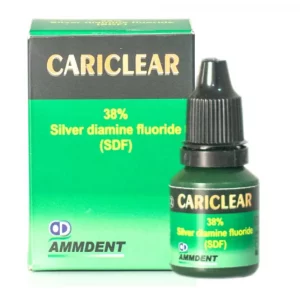

Cariclear features a potent 38% Silver Diamine Fluoride (SDF) solution, renowned for its multifaceted benefits in dental treatment. With its unique formulation, Cariclear serves as a powerful cariostatic agent, effectively inhibiting the progression of caries and promoting dental health.

Packaging-

- 1 x 5ml